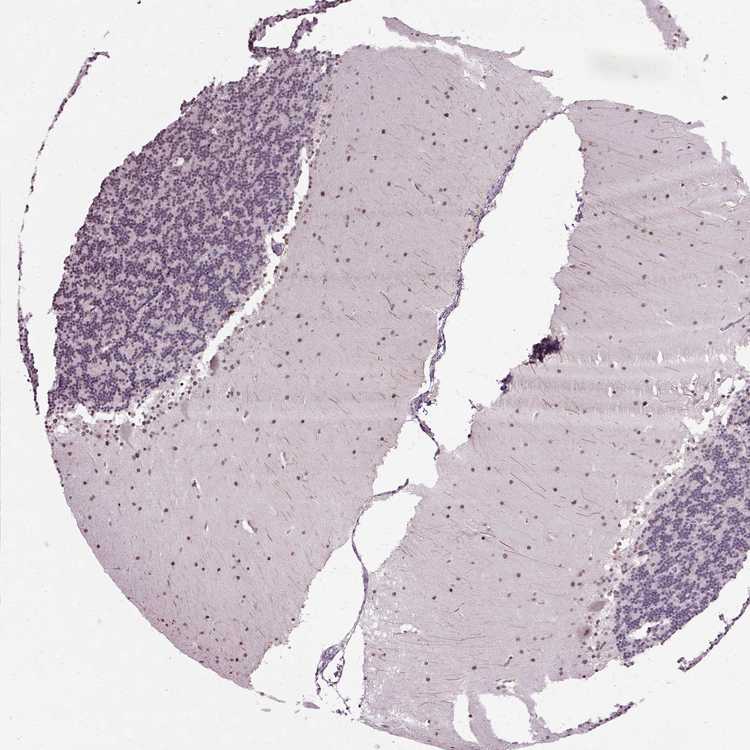

CEREBELLUM - Antibody stainingi

Antibody staining in the annotated cell types in the current human tissue is reported as not detected, low, medium, or high, based on conventional immunohistochemistry profiling in selected tissues. This score is based on the combination of the staining intensity and fraction of stained cells.

Each image is clickable and will lead to virtual microscopy that enables deeper exploration of all samples and also displays staining intensity scores, fraction scores and subcellular localization as well as patient and tissue information for each sample.

Antibody HPA019730

Purkinje cells Medium

Cells in granular layer Low

Cells in molecular layer Medium